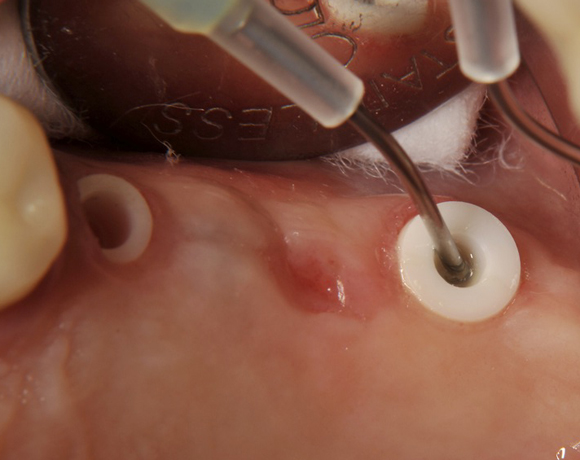

Im vorliegenden Patientenfall wurden für die Zähne 25 und 27 jeweils ein Implantat gesetzt. Nachdem die Implantate eingeheilt waren, wurde 25 – 27 mit einer Brücke versorgt.

Der operative Teil